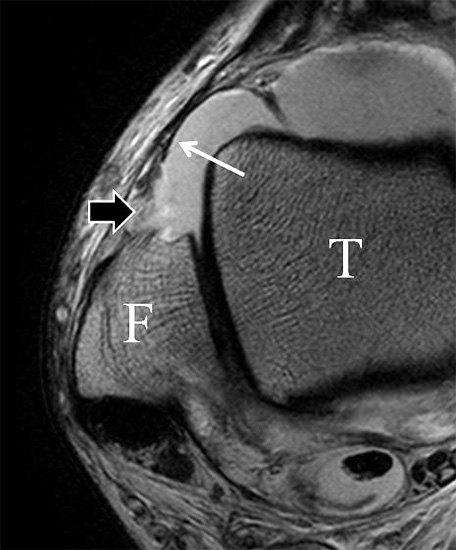

Das Ligamentum tibiofibulare posterius (hintere Syndesmose) verläuft flacher und geht nach kranial in das Ligamentum tibiofibulare interosseus und nach kaudal in das Ligamentum intermalleolare posterius über. Letzteres bildet ein artikuläres Labrum zwischen Trochlea und Talus 9.

Da also die hintere Syndesmose an der posterioren Tibia inseriert, entspricht eine Fraktur oder Infraktion des hinteren Volkmann`schen Dreiecks funktionell einem knöchernen Ausriss des Ligamentum tibiofibulare posterius (Abb. 18 a und b). Aufgrund der Koinzidenz von Syndesmosenläsionen mit Innenbandverletzungen ist bei der Beurteilung gesondert auf solche zu achten.